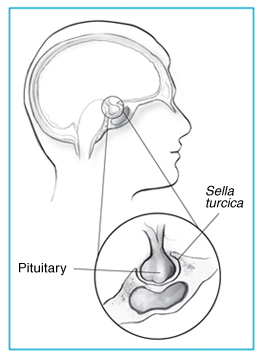

- Physical and Hormonal Maturation: He experienced a 3-inch growth spurt in four months and developed facial hair and mature genitalia — attributed to stimulation of the pituitary gland via expansion of the sella turcica (a bone cavity housing the pituitary gland)